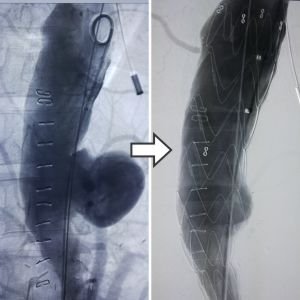

Covered Stent (EVAR or TEVAR for Aortic aneurysm and dissection)

Aortic aneurysms and dissection are life threatening diseases with very high morbidity & mortality rates when treated by surgery. We can offer less invasive treatment by EVAR/TEVAR with less incidence of complications.